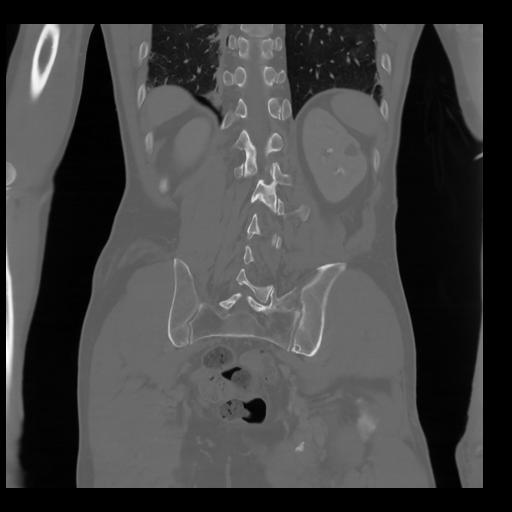

35 CUERPO,CE,Coronal,3.000,CUERPO,Coronal,